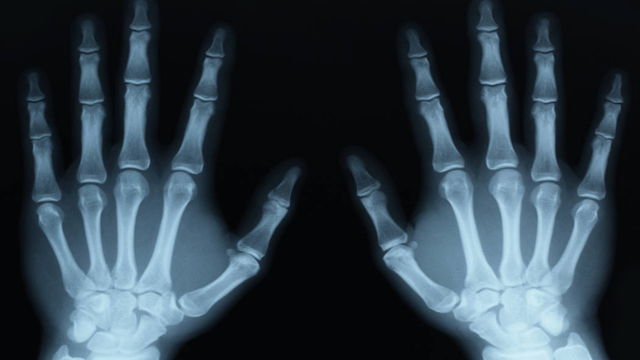

5. Tia X

Đây không phải là sóng điện từ đầu tiên tình cờ được phát hiện.

Tối ngày 8/11/1895 khi Wilhelm Roentgen đang tiến hành một thí nghiệm sử dụng tia âm cực, ông chợt phát hiện ra một số mảnh bìa các-tông nhiễm huỳnh quang trong phòng sáng rực lên cho dù giữa các tia âm cực và những tấm bìa các-tông đó có vật ngăn cách rất dày.

Cách giải thích duy nhất là tia sáng đó đã xuyên qua vật ngăn cách cứng. Roentgen đã tìm ra tính chất của thứ tia bí mật mà ông tạm đặt tên là tia X và chính nó đã mang lại cho ông giải Nobel về vật lý đầu tiên vào năm 1901.